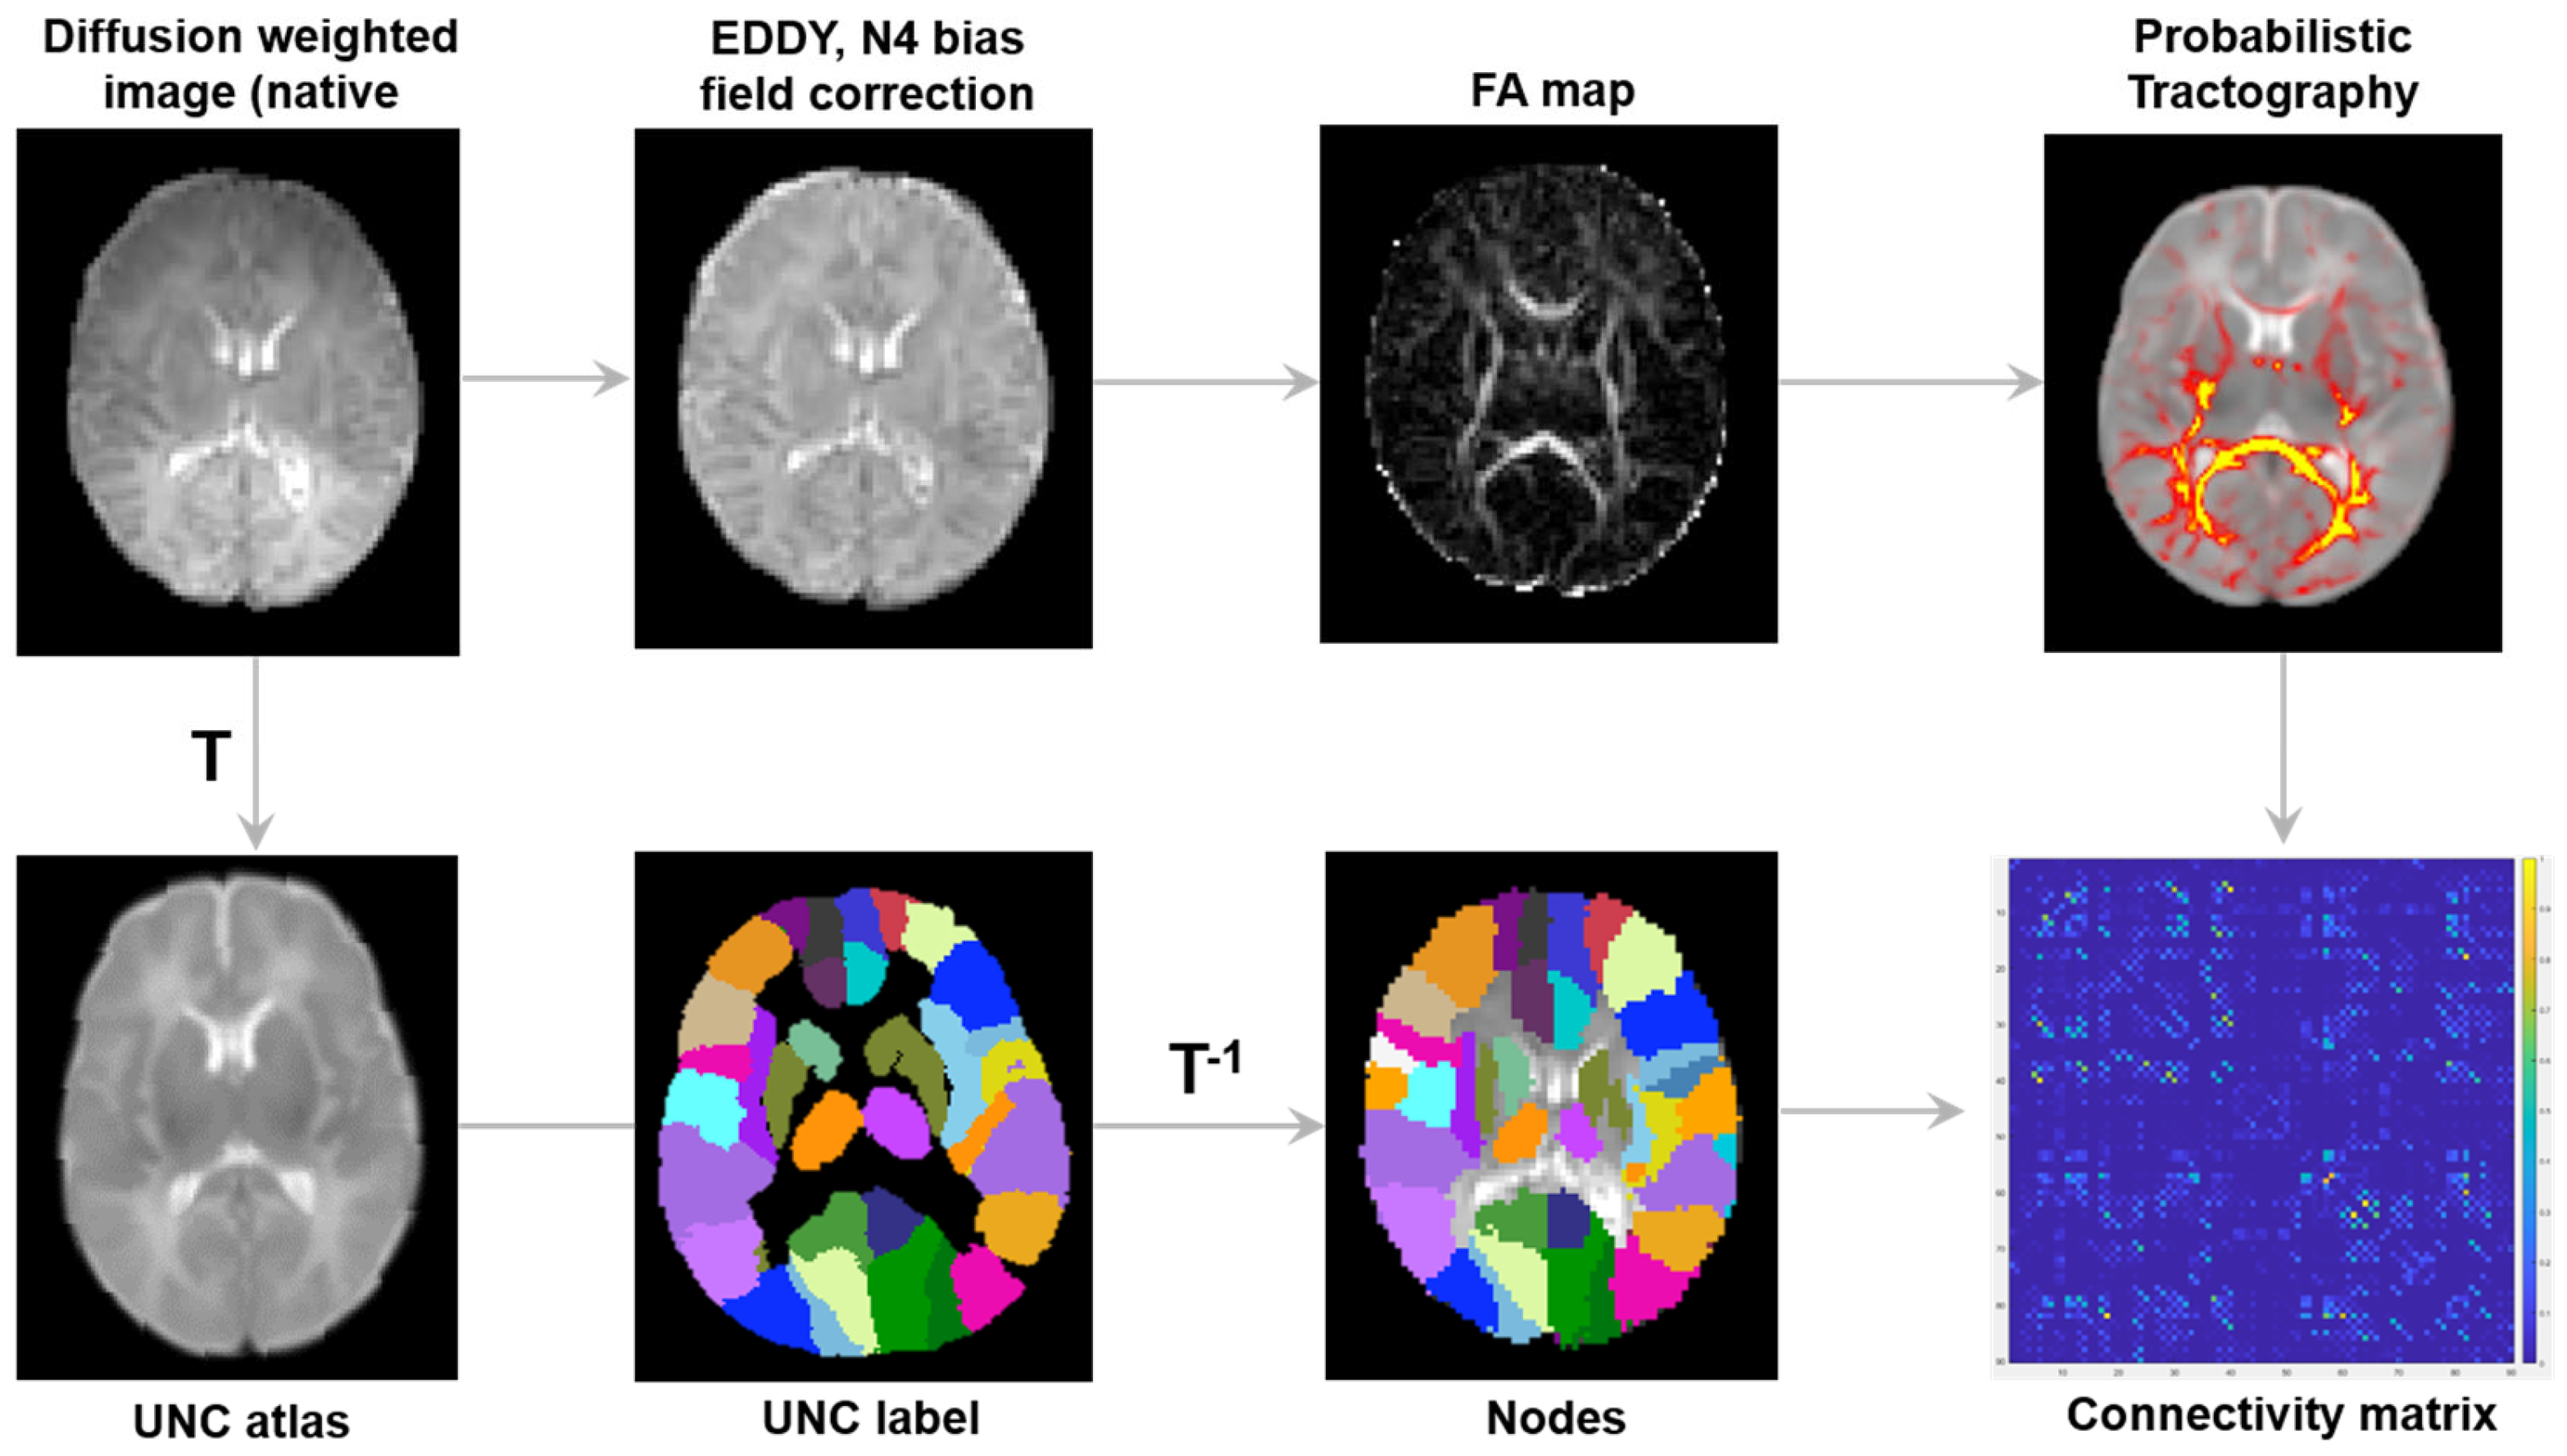

2.4. Image Processing

2.5. Network Construction